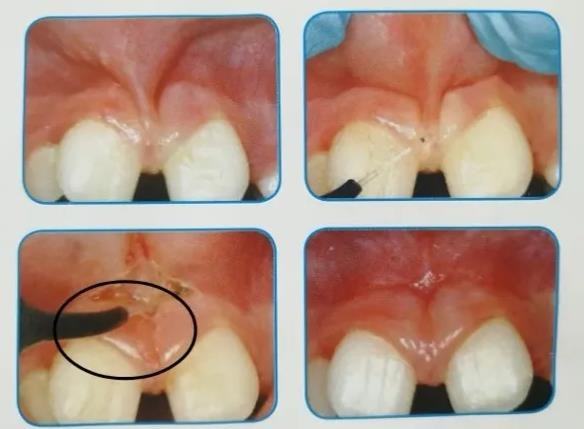

01.软组织手术

包括唇舌系带矫正术、种植牙二期手术、牙龈手术(牙龈切除、牙龈修形)、良性小肿瘤切除、口腔粘液腺囊肿以及白斑或扁平苔藓的切除。激光代替了传统的手术刀,切割更精确,术中不出血、视野清楚、不需要缝合,可以即刻进行下一步操作,术后反应小。术中可以少用甚至不用麻醉。由于激光有消毒作用,也同时降低了术后伤口感染的风险。